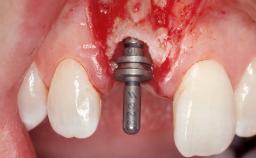

Immediate Flapless Placement of an Implant in a Maxillary Left Central Incisor Site

Placement Protocol Immediate implant placement

Tooth Site Maxillary incisor or canine

Socket Morphology Single-root socket

Socket Integrity Damage to one or more bone walls

Bone Volume Damage to one or more socket walls